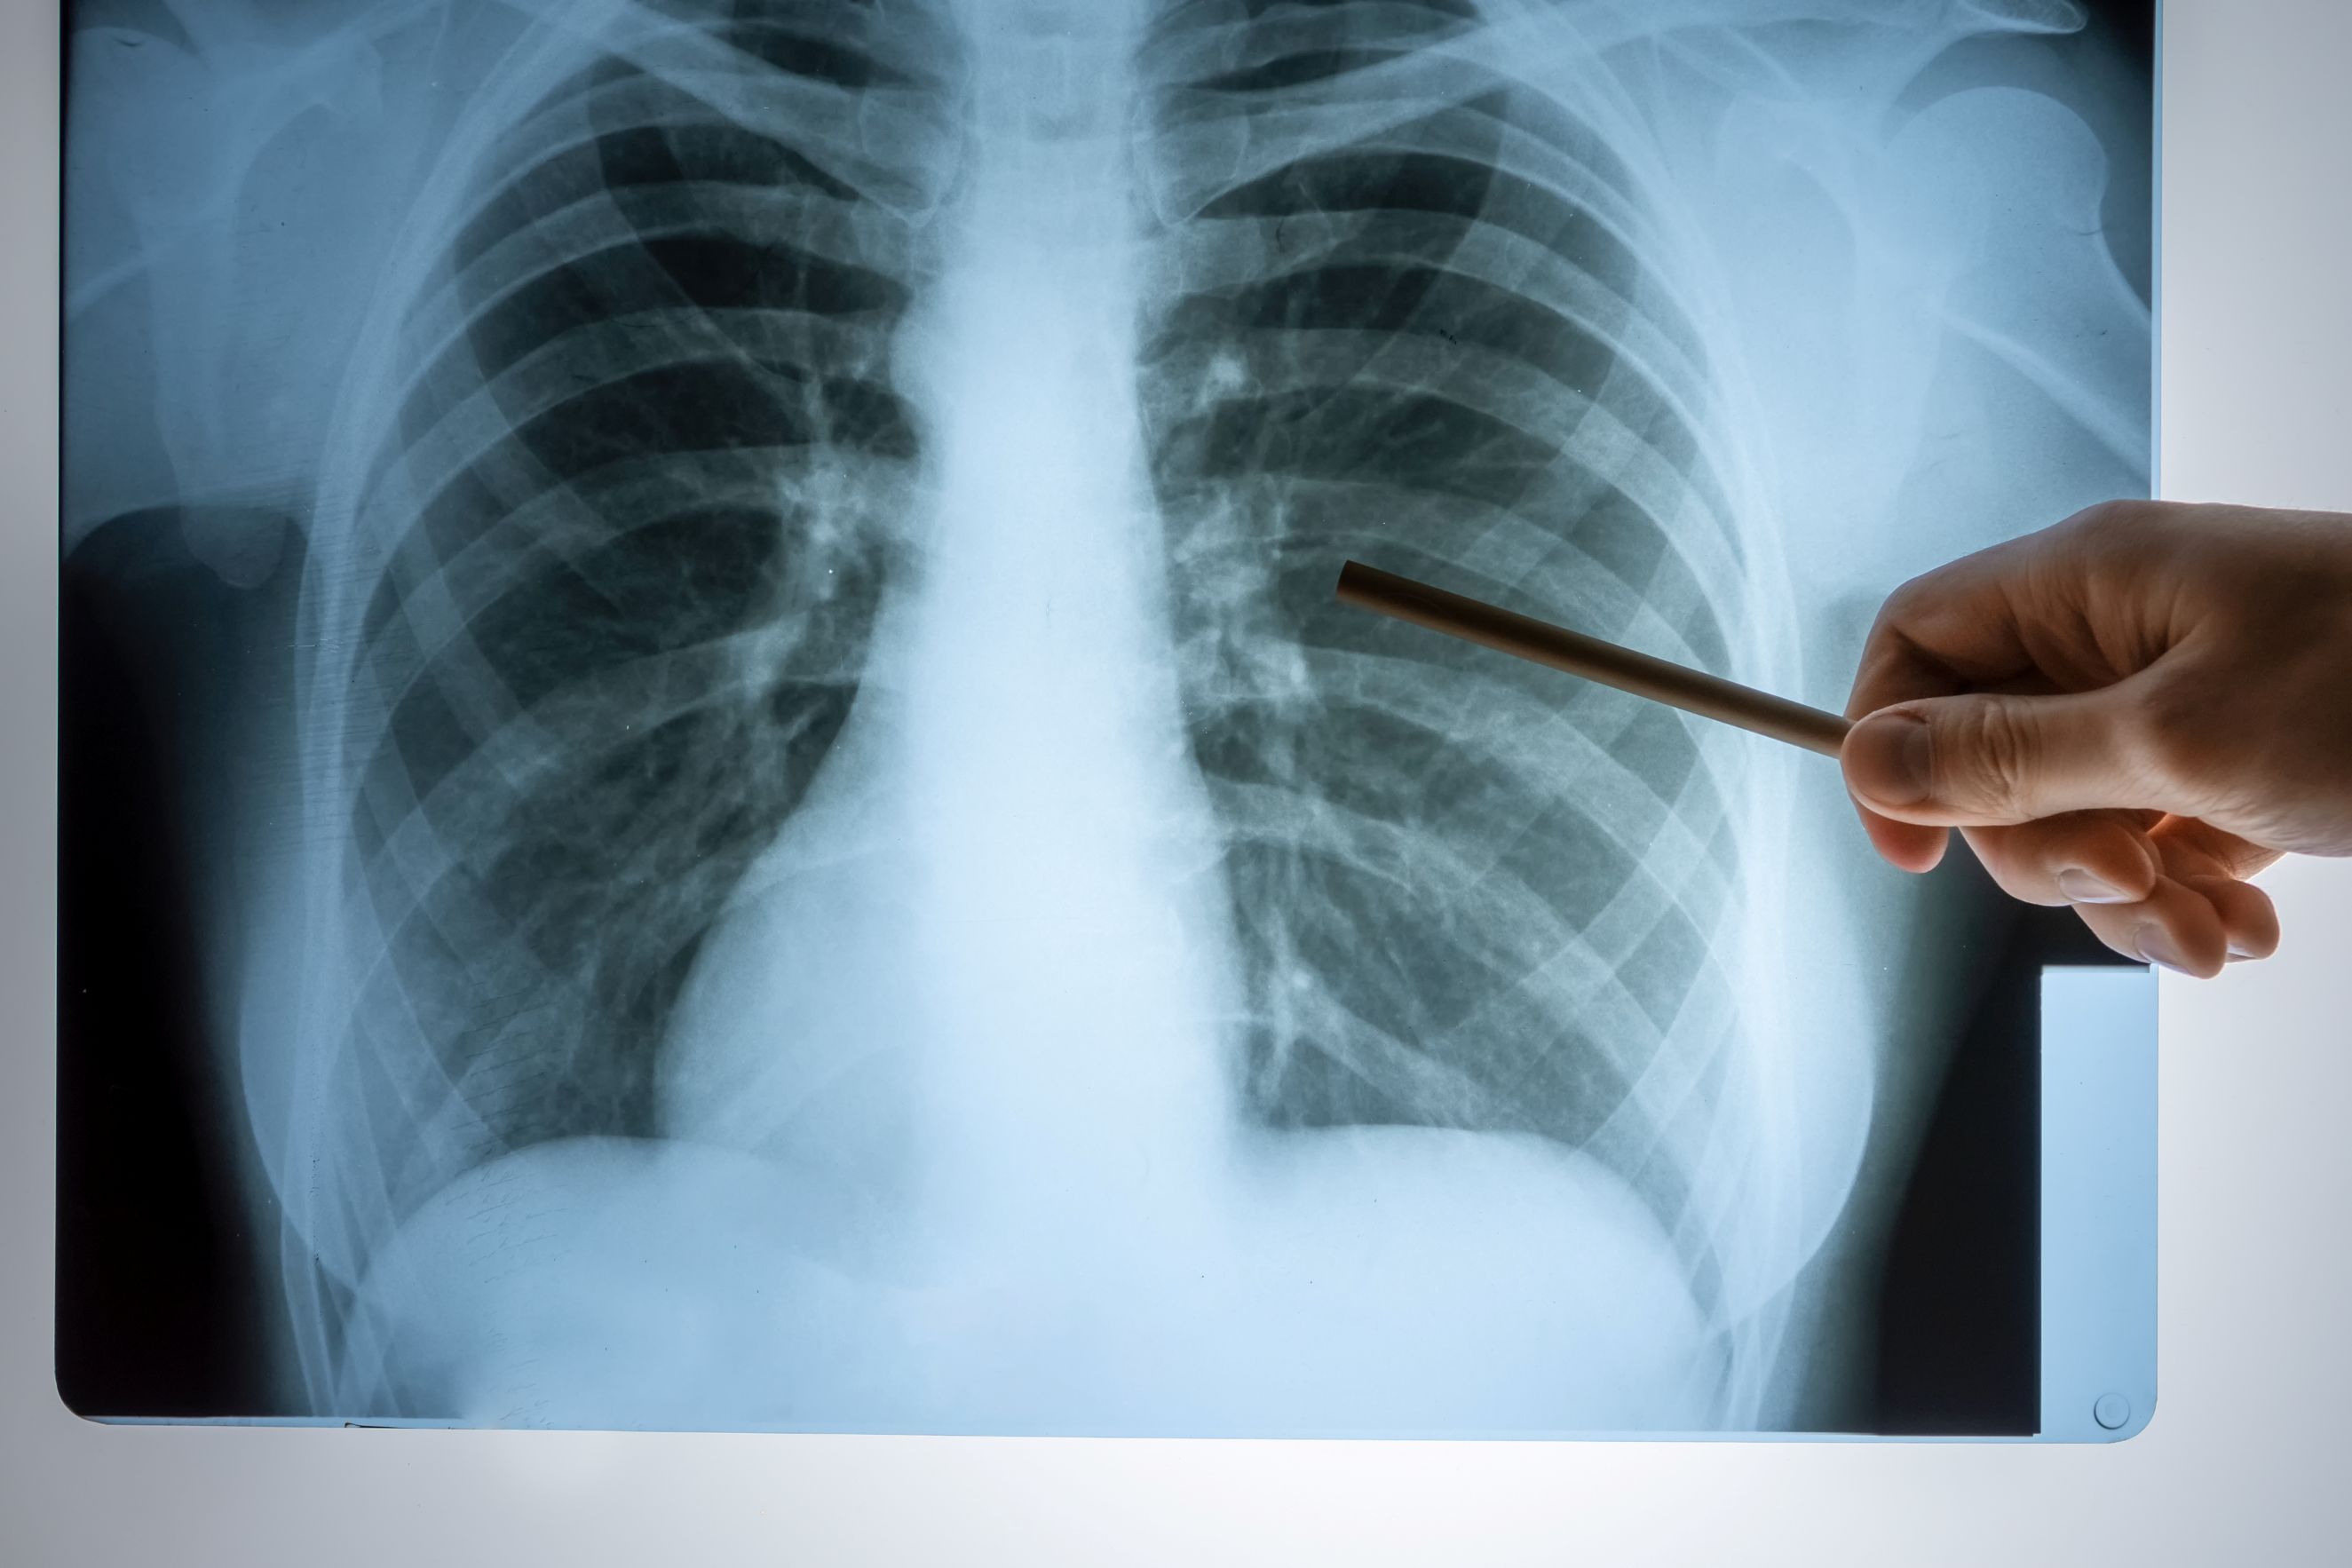

La neumonía es una infección que afecta los pulmones y puede causar complicaciones graves si no se atiende a tiempo. Esta enfermedad puede ser causada por diferentes tipos de bacterias, virus y hongos, por lo que es fundamental conocer cómo prevenirla y manejarla correctamente.